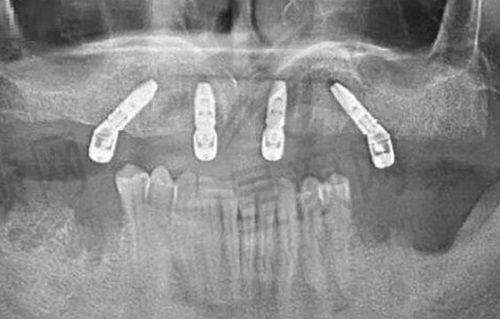

深圳佳乐口腔诊所的地理位置十分优越,它位于龙岗区泽福路 39 号。如果您对这个位置不太熟悉,不用担心,开个导航就能轻松找到。诊所的科室非常齐全,开展的项目丰富多样。不仅仅局限于洗牙、牙痛治疗等基础项目,还可以进行种植牙、牙齿矫正、儿童口腔等较为复杂的治疗。这对于不同年龄阶段、不同牙齿问题的患者来说,无疑是一个福音。而且,佳乐口腔还提供免费停车服务,营业时间是从早上 9 点到晚上 19 点。这样的安排,方便了周边的居民,即使工作繁忙,也能在合适的时间前来就诊。

深圳佳乐口腔诊所属于口腔诊所类型。虽然目前显示医生人数为 0,但从实际情况来看,诊所拥有多位专精的牙医为患者服务。其擅长项目主要集中在牙齿方面,涵盖了从基础治疗到复杂矫正和种植的多个领域。